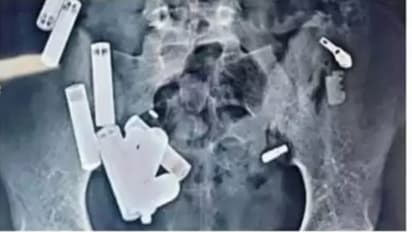

आग्रा. उत्तर प्रदेशातील हाथरस येथील १४ वर्षीय आदित्य शर्माचा दुःखद मृत्यू सर्वांना हादरवून टाकणारा आहे. दिल्लीतील सफदरजंग रुग्णालयात डॉक्टरांनी आदित्यच्या पोटातून पाच तासांच्या गुंतागुंतीच्या शस्त्रक्रियेत बॅटरी, साखळी, रेझर, ब्लेडचे तुकडे आणि स्क्रू यासह ६५ वस्तू काढल्या. मात्र, शस्त्रक्रियेनंतरही डॉक्टर त्याला वाचवू शकले नाहीत आणि संसर्गाने त्याचा मृत्यू झाला.

आग्रा येथील उपचारानंतर आदित्यला जयपूरच्या रुग्णालयात रेफर करण्यात आले होते, जिथे अनेक चाचण्या आणि स्कॅननंतर त्याला परत उत्तर प्रदेशात पाठवण्यात आले. दोन दिवसांनी त्याची प्रकृती पुन्हा बिघडल्याने त्याला अलिगढच्या रुग्णालयात नेण्यात आले. तिथे डॉक्टरांनी त्याच्या नाकातील अडथळा यशस्वीरित्या काढून टाकला, परंतु त्याच्या पोटात असामान्य वेदना होत असल्याने २६ ऑक्टोबर रोजी व्यापक अल्ट्रासाऊंड करण्यात आले. या चाचणीत १९ अज्ञात वस्तू दिसल्या, ज्या पाहून डॉक्टरांनी त्याला तातडीने नोएडाच्या रुग्णालयात रेफर केले.

नोएडामध्ये डॉक्टरांनी तपासणी दरम्यान त्याच्या पोटात आणखी ४२ वस्तू आढळल्या, ज्यामुळे त्याला तातडीने दिल्लीतील सफदरजंग रुग्णालयात नेण्यात आले. तिथे डॉक्टरांना स्कॅनमध्ये "एकूण ६५ वस्तू" आढळल्या आणि या स्थितीत त्याची हृदयाची गती प्रति मिनिट २८० पर्यंत पोहोचली होती. पाच तासांच्या शस्त्रक्रियेनंतरही डॉक्टर त्याला वाचवू शकले नाहीत आणि त्याचा दुःखद मृत्यू झाला.